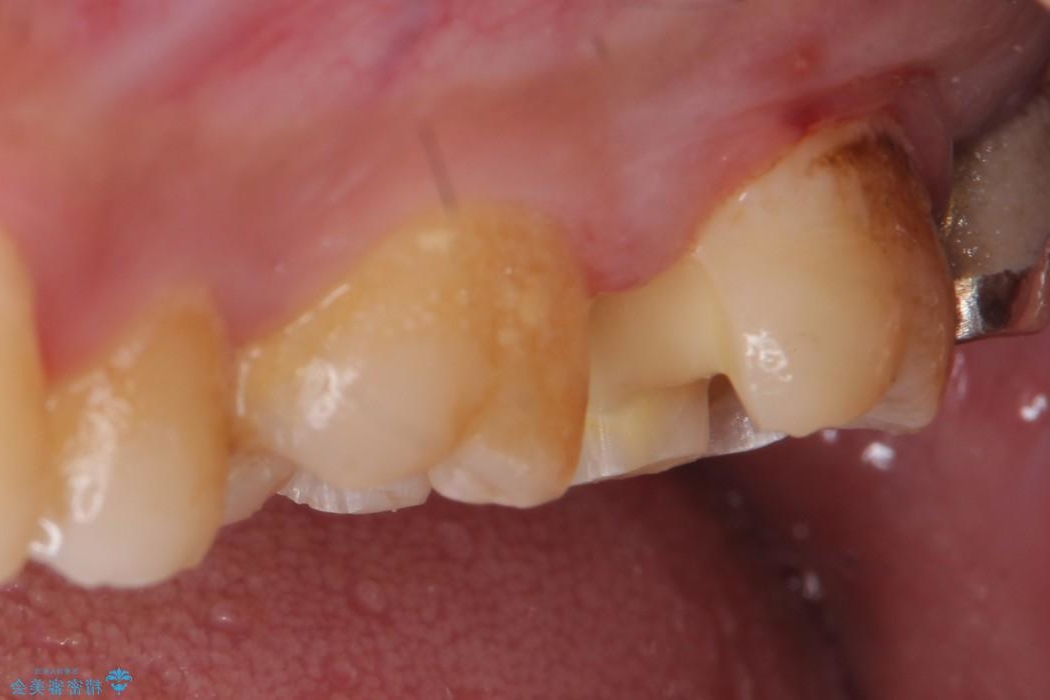

左上の他院で治療した銀歯の見た目が気になり白いものへ変えたいとの主訴で来院されました。

古い詰め物を外し、白く審美性の高いセラミックインレーにて再治療を行うこととしました。